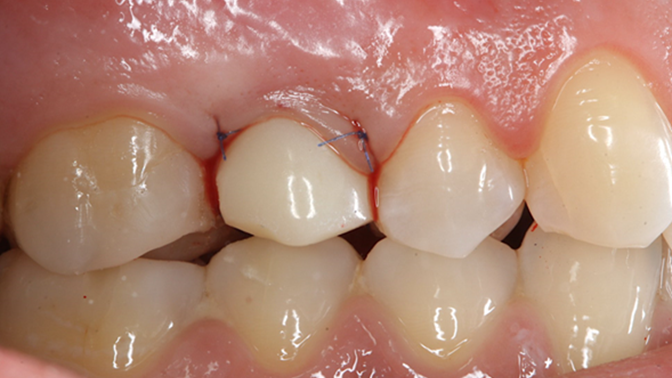

“Patient’s smile was recovered on the day of surgery

with reliable & highly-aesthetic results using AnyRidge & R2GATE. ”

Clinical case: AnyRidge immediate loading

- Courtesy of Dr. Andres Paraud Freixas, Chile -

AnyRidge, ISQ value, initial stability, immediate loading, KnifeThread, maxillary anterior, Mega ISQ, Dr. Andres Paraud Freixas

AnyRidge implant system, Mega ISQ, Digital prosthesis